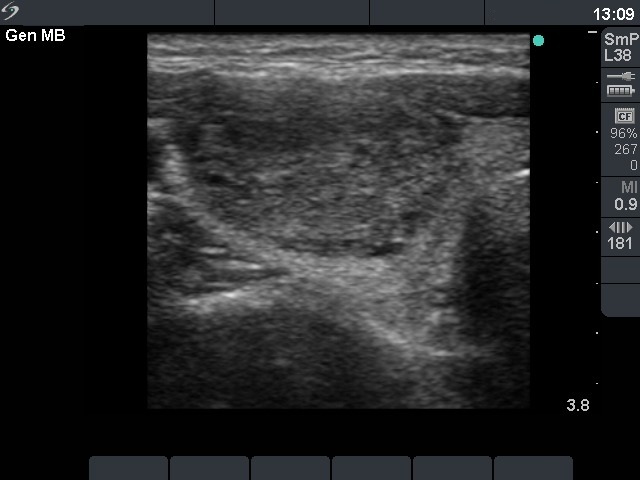

Ultrasonography: the thyroids were echonormal. There was a moderately hypoechogenic nodule displaying both perinodular and intranodular blood flow.